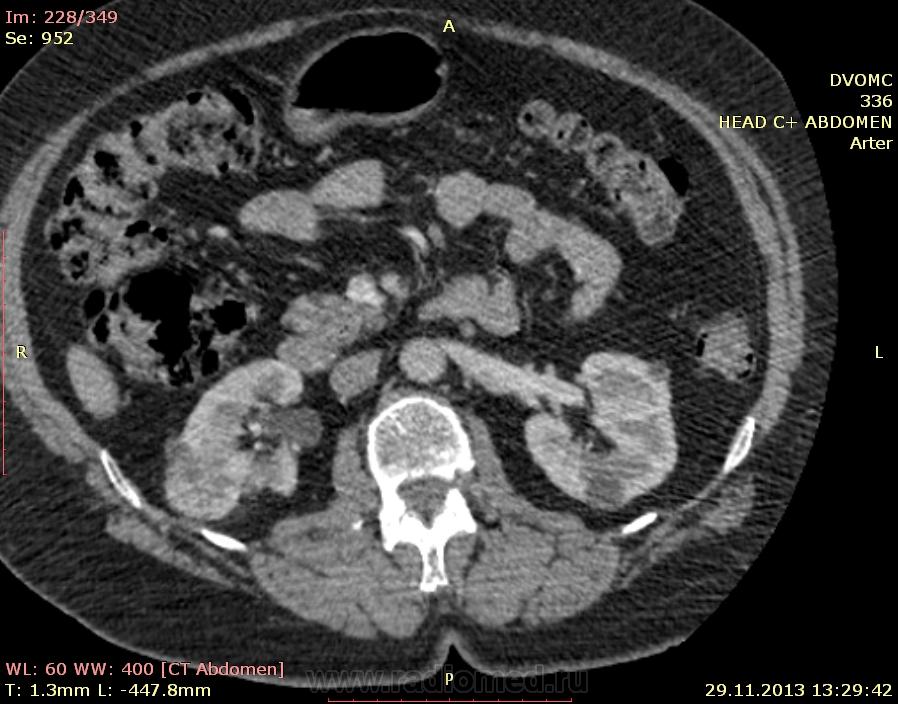

Пациентка 66 лет. В 2010 году мастэктомия слева - Cr II B ст., псориаз. Я нашел: образование нижнего полюса правой почки, образование в антральном отделе желудка по малой кривизне, киста яичника слева...в желчном пузыре много газосодержащих камней(?), лимфоузлов вроде не видно. Всё, кроме образования желудка находили ранее на УЗИ да на МРТ. Коллеги, посмотрите, можт я чё пропустил или неправильно понял. Какие мысли по поводу образований - особенно желудка(GIST? mts?)  DICOM здесь http://files.mail.ru/2C4F7CA79A884D37B3C86FF69C3D8D67

Мне кажется, что маловато контраста на вес пациентки. Почечно-клеточная (как более вероятная) карцинома правой почки, в стенке желудка написала бы мтс. Газосодержащие камни желчного пузыря. Кистовидное образование яичника. Киста печени, кисты почек. Дивертикулез толстой кишки. А что с жиром в грыже (вроде пупочная))) - наверное, последствие инфаркта сальника.